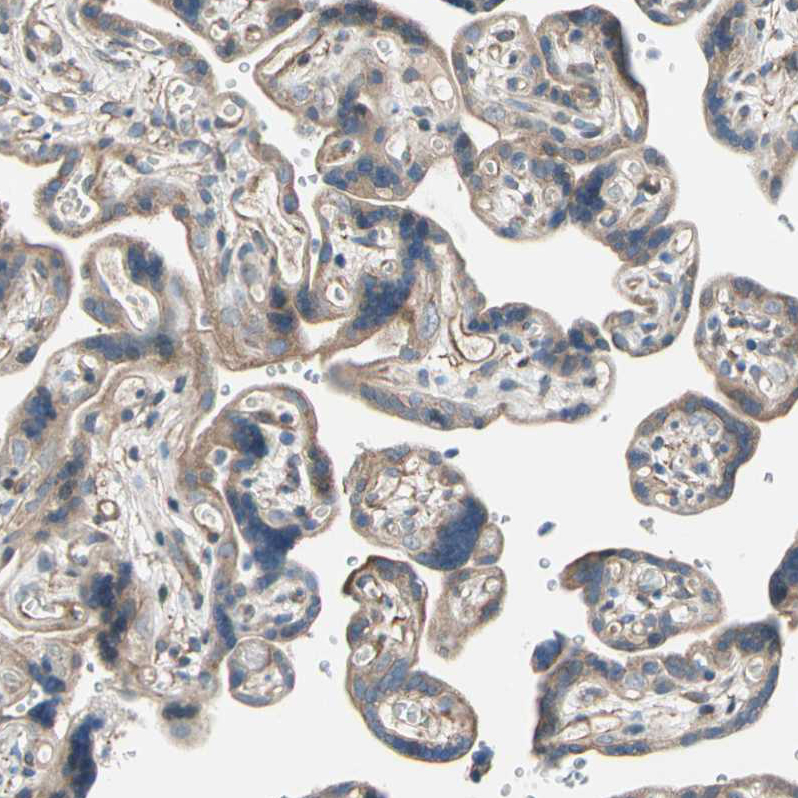

Immunohistochemical staining of human placenta shows weak to moderate cytoplasmic positivity in trophoblastic cells.